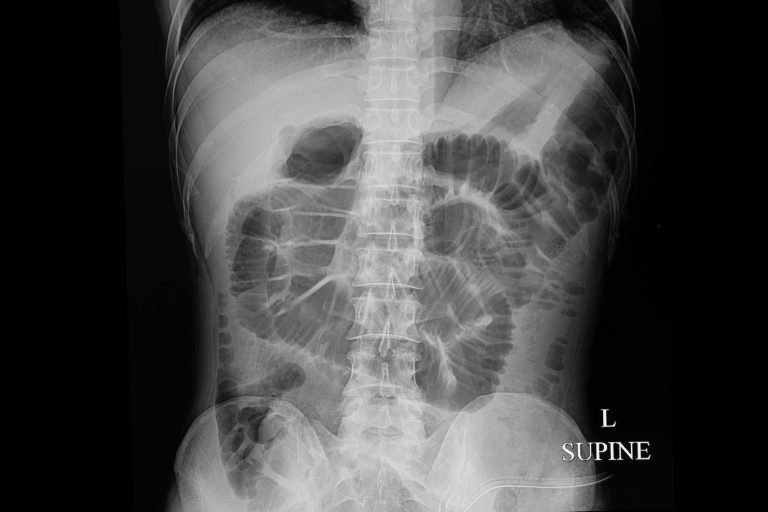

Kleinen Darmverschluss (Film RöntgenAbdomen (Rückenlage) Show Dünndarm und Magen dehnen